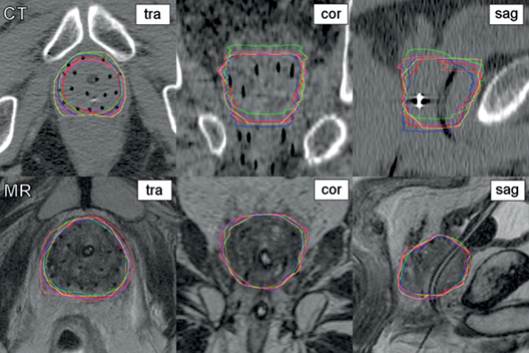

Las causas mostradas en la tabla 1 permiten inferir aspectos que en las referencias confirman las probables soluciones para estas prioridades de los modos de fallos. La solución a la disminución de las incertidumbres en el delineado del blanco están asociadas a tres grandes áreas: optimización de las imágenes, establecimiento de protocolos y guías de delineación y entrenamientos especializados. 3,4 Respecto a la optimización de imágenes, el primer modo de fallo muestra el empleo de técnicas de imágenes alternativas como el FDG-PET. Entre las ventajas potenciales de las imágenes funcionales están la reducción de la variabilidad interobservador, la identificación de extensiones tumorales pasadas por alto en TC y/o RM y, posiblemente, la identificación de subvolúmenes GTV que requieren una dosis de radiación más alta. Entre las causas enunciadas en la tabla 1 aparecen fallos de procedimientos. A modo ilustrativo, la figura 4 muestra la variabilidad interobservador para la delimitación de la próstata. En la figura se muestran imágenes de resonancia magnética (RM) y de TC en diferentes planos del mismo paciente. Las aclaraciones TRA, COR y SAG significan, respectivamente, transversal, coronal y sagital. Se aprecia que la variabilidad al definir el vértice, la base y los bordes laterales de la próstata, se reduce con el empleo de las imágenes por RM. (Fig. 4).